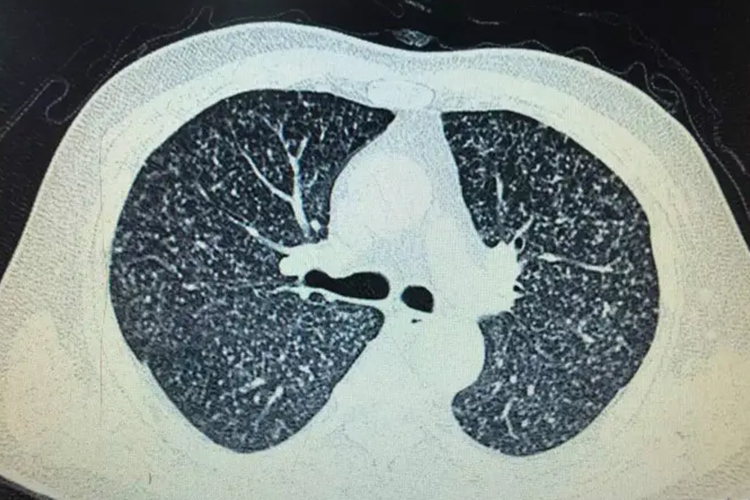

CT图像是经数字转换的重建模拟图像,是由一定数目从黑到白不同灰度的像素按固有矩阵排列而成。这些像素的灰度反映的是相应体素的X 线吸收系数。CT图像用灰度反映器官和组织对X线的吸收程度。如含气的肺组织吸收X 线少,在CT图像上呈黑色影像,即低密度影像;肌肉或脏器等软组织,吸收中等剂量的X线,呈灰色影像,即中等密度影像;骨组织含钙量高,吸收线多,呈白色影像,即高密度影像。

CT图像为断层图像

CT图像常规是横轴位断层图像,克服了普通X线检查各组织结构影像重叠的缺点,从而使各个器官组织结构得以清楚显示,提高了病灶的检出率。在CT扫描的基础上,利用计算机软件对CT轴位断面图像信息进行图像重组,可获得冠状位、矢状位二维图像以及三维立体的CT图像等,称为CT图像后处理技术。